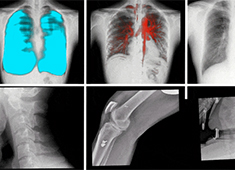

影響DR圖像質(zhì)量的因素有哪些方面

哪些因素會影響DR圖像質(zhì)量呢?普愛醫(yī)療歸納了以下幾大因素。當(dāng)前國產(chǎn)DR都尤其重視圖像后處理系統(tǒng)的升級,如普愛醫(yī)療研發(fā)生產(chǎn)的多功能動態(tài)DR(型號:PLX8100),應(yīng)用了公司自主研發(fā)的組織均衡技術(shù),它是基于低灰度區(qū)擴(kuò)展到高...

百微米DR的臨床優(yōu)勢:呈現(xiàn)更豐富的成像細(xì)節(jié)

目前市面上已經(jīng)開始漸漸流行“百微米DR”,百微米DR好在哪里,具有什么樣的臨床優(yōu)勢?以PERLOVE品牌的PLX8100為例,這是一款大尺寸的多功能動態(tài)DR機(jī),搭載了高性能的百微米平板,4K*4K采集矩陣與100μm像素...